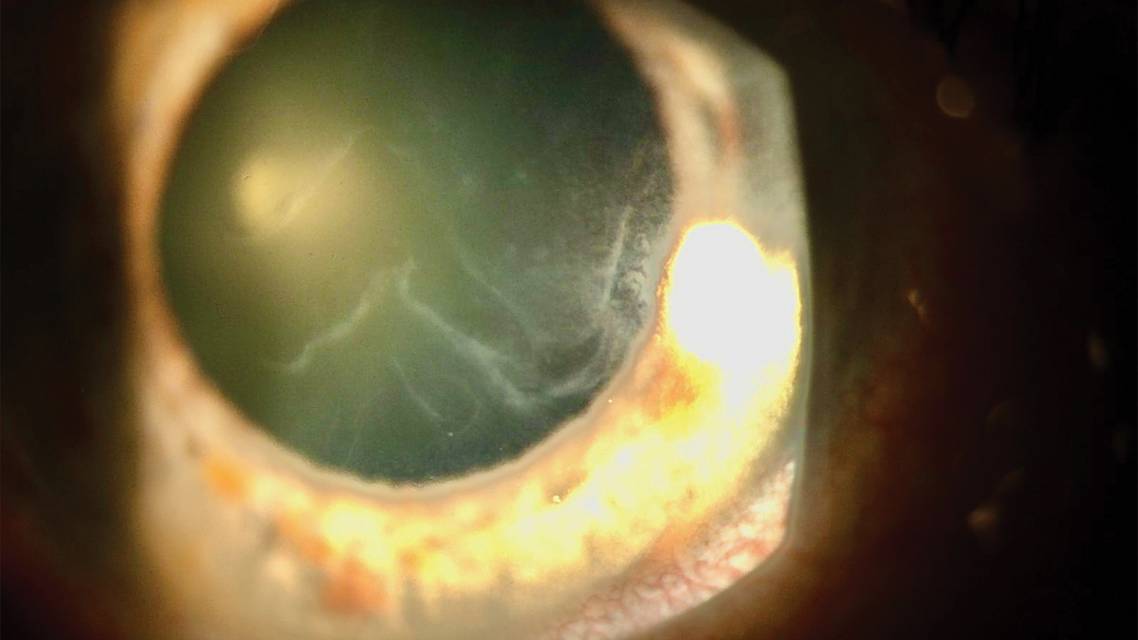

EBMD can be subtle and difficult to detect, even with use of vital dyes (Figure), because of the wide spectrum of disease presentation and the quick-healing nature of the corneal epithelium. In these instances, the corneal sweep test described by D. Brian Kim, MD, may bridge the gap in our diagnostic toolkit for corneal erosions.5 Dr. Kim developed the Kim Corneal Sweeper (Katena Products) to help aid in this diagnosis.